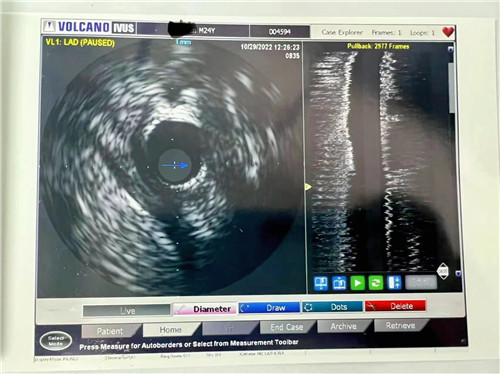

血管內(nèi)超聲提示血管斑塊負(fù)荷66.1%

小貼士:血管內(nèi)超聲(IVUS)

血管內(nèi)超聲(IVUS)是利用導(dǎo)管將一高頻微型超聲探頭導(dǎo)入血管腔內(nèi)進(jìn)行探測(cè),再經(jīng)電子成像系統(tǒng)來(lái)顯示心血管組織結(jié)構(gòu)和幾何形態(tài)的微細(xì)解剖信息。它能彌補(bǔ)CAG的不足之處,不僅可準(zhǔn)確測(cè)量管腔及粥樣斑塊或纖維斑塊的大小,更重要的是可提供粥樣斑塊的大體組織信息,在顯示因介入治療所致的復(fù)雜病變形態(tài)時(shí)明顯優(yōu)于造影。